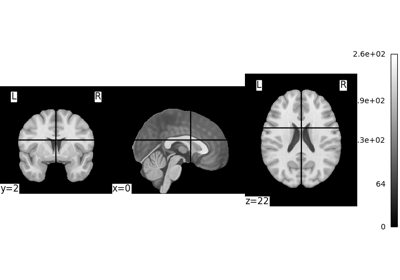

Let’s have a look at this image:

nilearn.plotting.plot_img(nilearn.datasets.MNI152_FILE_PATH)